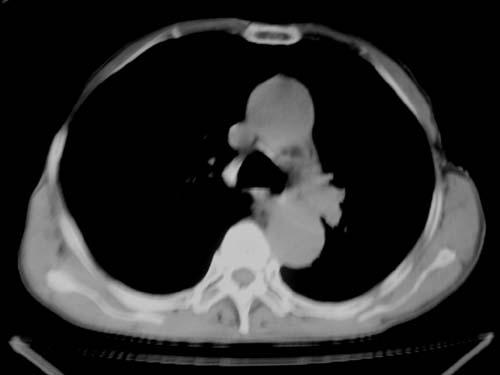

标题: CT19736:男,76岁,咳嗽,胸痛 [打印本页]

标题: CT19736:男,76岁,咳嗽,胸痛

支持左上肺周围型肺癌性并空洞形成伴胸椎转移。

左上沟癌空洞形成并胸椎转移。

考虑癌性空洞并胸椎转移。

空洞内壁有多发结节,支持癌性空洞。

支持左上肺周围型肺癌并空洞形成伴胸椎转移。z左下肺炎

左上肺癌性空洞伴胸椎转移。